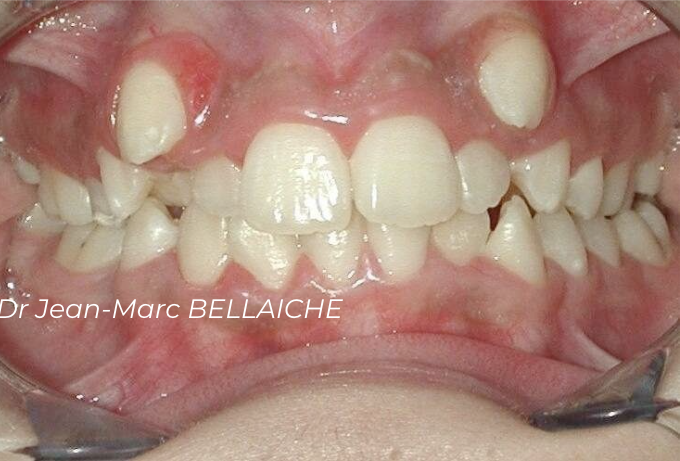

Cas 3 : Encombrement avec recouvrement incisif

Situation "Avant Traitement" : cas d'encombrement associé à un recouvrement excessif des incisives supérieures sur les inférieures.

Ce type de malocclusion peut nuire aux fonctions occlusales normales et peut être à l'origine de "déchaussements".